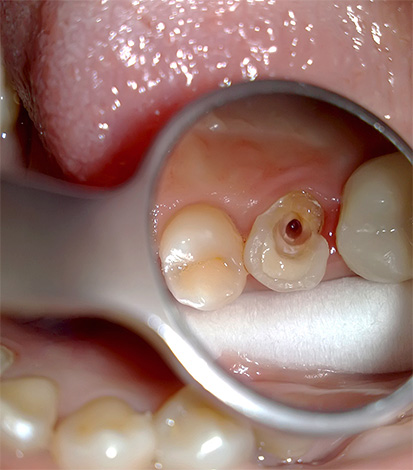

Un microscopio in endodonzia viene utilizzato, in particolare, per diagnosticare il numero di canali radicolari e la qualità del loro passaggio. Il trattamento della pulpite di un dente a tre radici al microscopio consente di trovare e trattare rapidamente anche i passaggi più difficili e ci sono molti casi simili nella pratica di un dentista.

Un microscopio endodontico ci consente di dire con quasi il 100% di certezza alla fine del trattamento che tutti i canali sono stati passati e correttamente sigillati. È lui che ti consente di controllare ogni fase del trattamento della pulite, prevenendo ulteriori complicazioni. Il trattamento tradizionale senza l'uso di un microscopio è spesso associato alla presenza di conseguenze negative a lungo termine, ad esempio a causa del fatto che il medico semplicemente non ha potuto vedere il canale aggiuntivo nel dente e lo ha perso durante il trattamento, lasciando una polpa infetta al suo interno.

A volte, durante il trattamento della pulpite, il medico trova 3 canali, ma in realtà c'è un quarto canale (o addirittura un quinto) "ben nascosto" nel dente. Ci sono casi in cui non manca un canale, ma diversi, poiché ci sono opzioni complesse per la loro posizione nel dente.